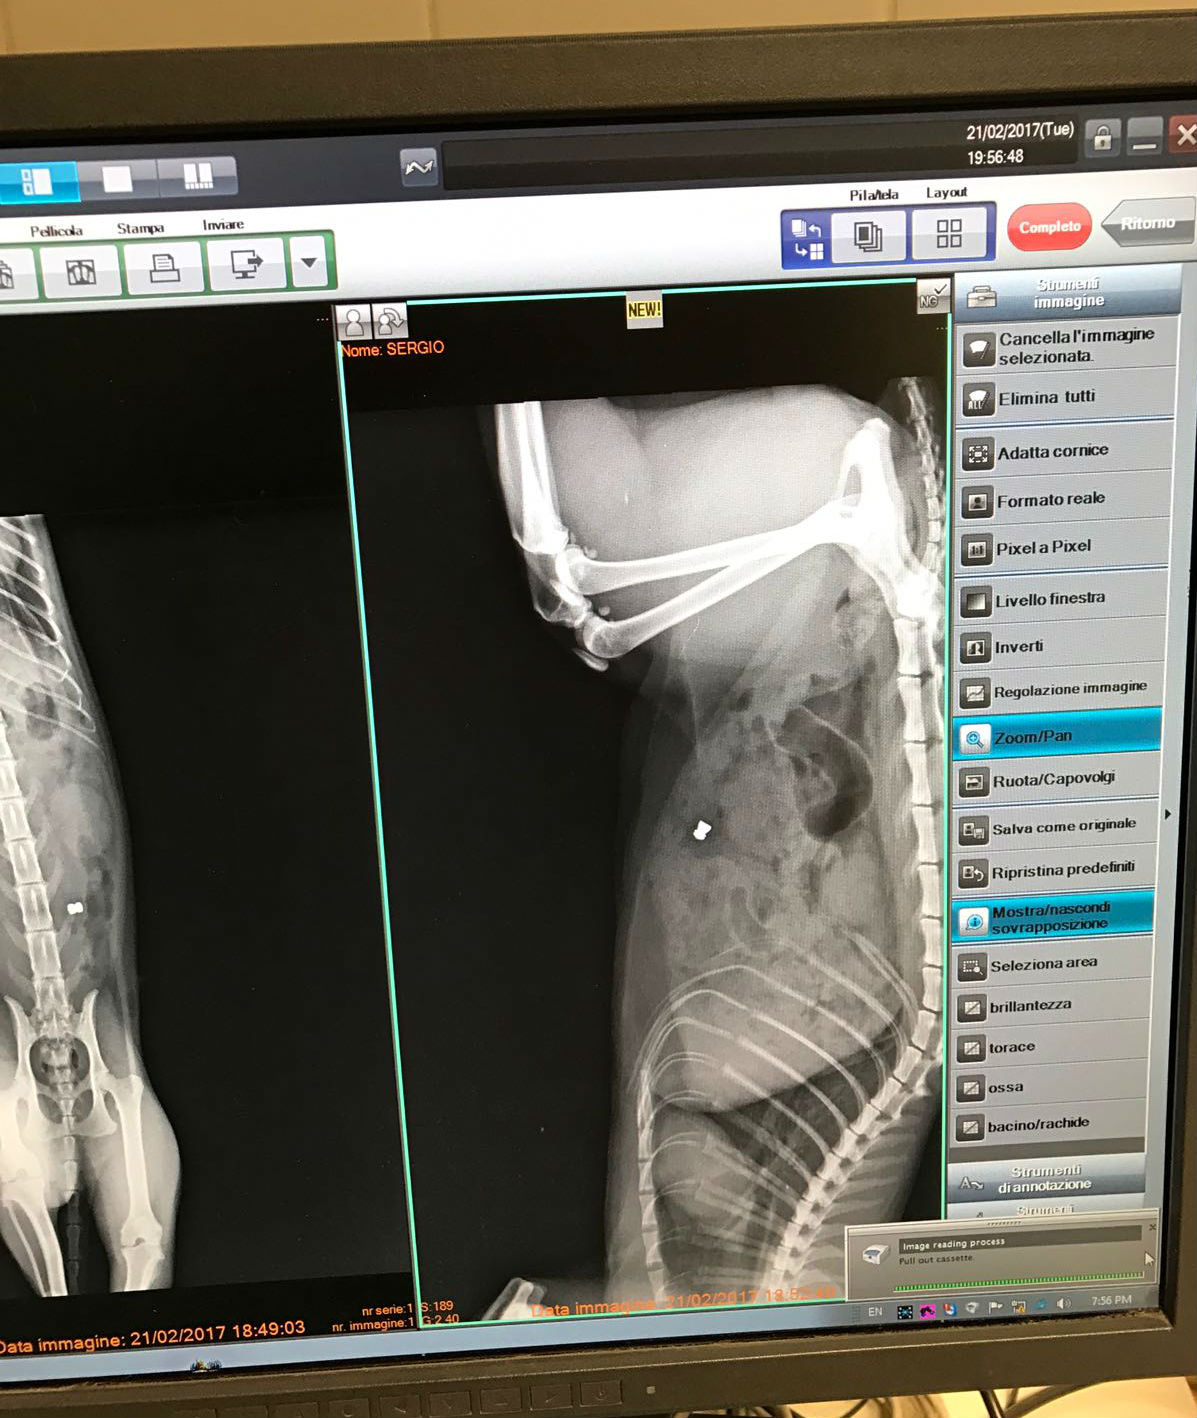

E’ stato quindi deciso di approfondire con una lastra, solo allora è emersa la realtà: Sergio aveva un foro nello stomaco ed un piombino conficcato all’interno. Al tatto non era percettibile visto che la ferita superficiale si era velocemente rimarginata. A quel punto è scattata l’operazione per cercare di salvargli la vita. Soltanto nei prossimi giorni si saprà se riuscirà a superare il pesante intervento chirurgico (nel corso del quale gli è stata asportata una parte dell’intestino) e l’infezione provocata dal piombino.

Spiega Matteo: “Dalle lastre e dai segni lasciati, gli hanno sparato con una carabina ad aria compressa usando proiettili di piombo. Non sembra quindi il gioco incosciente di un bambino (che difficilmente avrebbe accesso ad una simile arma, ndr). Deve essere stato qualche bastardo che probabilmente ha sparato dalle finestre: ce ne sono molte che si affacciano sul giardino e di fronte a casa nostra”.